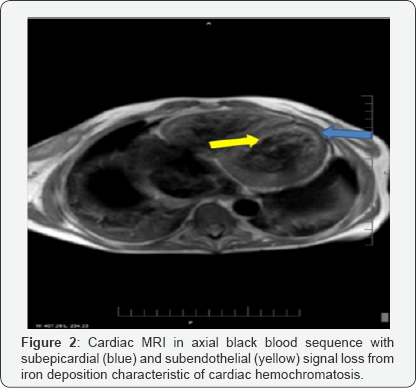

The patient had a recent hospital admission during which she was newly diagnosed with advanced CHF. BNP was 7062pg/ mL, Ferritin 30,044ng/mL, Transthoracic ECHO showed severe 4-chamber dilatation, with a left ventricular ejection fraction (LVEF) of 15% and global LV hypokinesis. Due to suspicion of cardiac hemochromatosis, a cardiac MRI was obtained, showing myocardial iron overload with severe biventricular dysfunction (Figure 2).